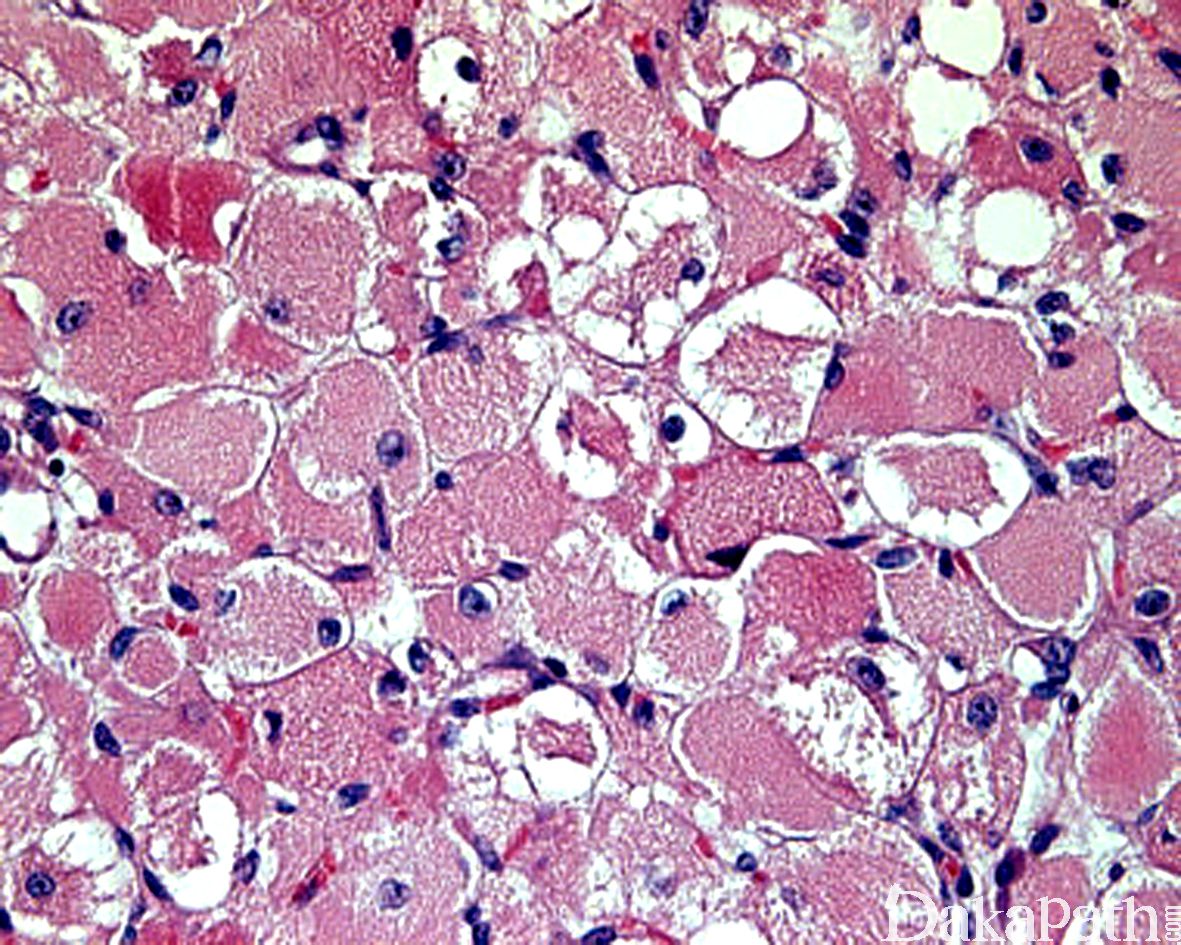

瘤细胞体积大,边界清楚,胞质丰富,嗜伊红色、颗粒状或透亮,有时可见胞浆透亮细胞中央有少量深嗜伊红色的胞质呈细条索状向周边放射伸展,形成所谓的蜘蛛细胞;

部分细胞内可见横纹,或可见棒状或杂草样结晶样物;

瘤细胞的核小、圆形,染色质呈空泡状,可见小核仁,无或罕见核分裂像。